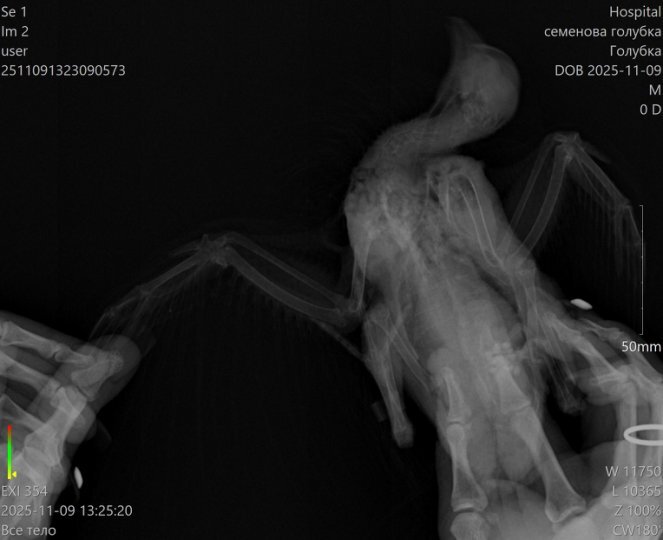

Когда приехали, ему сделали укол адреналина, чтобы стабилизировать сердце. Его состояние перестало быть таким тяжёлым, но было очевидно, что это не надолго. Сделали рентген. Почти все его лёгкие - сплошная метастаза. Ему просто нечем дышать.

Метастаза такого размера не появляется за неделю, две. Она была давно. Её можно было увидеть и оценить, переживёт ли он такую терапию. Почему никто её не увидел - я не знаю.

Перед БНЗТ мы сделали Стичу КТ (по своей инициативе, нас смутили такие низкие требования к процедуре). Это было до облучения.

На КТ не было обнаружено метастазов в лёгких, лёгкие были чистыми.

Метастазы такого размера, как на рентгене в последний день НЕ МОГУТ вырасти за неделю-две. Получается точнее будет это назвать острым патологическим процессом, произошедшим после терапии.

есть возможность, что до БНЗТ были только микроскопические метастазы, и их не могло быть видно, но даже они не способны за 12 дней заполнить лёгкие таким массивом ткани.

7 числа случилась острая дыхательная недостаточность, задыхался, пена изо рта, судороги. Когда сделали рентген, стало ясно, что лёгкие почти полностью забиты патологической тканью, газообмена не осталось, дышать просто нечем.

Т.е. чтобы поправить саму себя в своем же посте, уточняю: это была не опухоль, которая выросла,

а разрушение лёгких, произошедшее в течение тех самых 10-12 дней, когда никто не предупредил нас, что нужно делать КТ, рентген, анализы или обращаться срочно.

кт до бнзт - чистые лёгкие, метастазы размером на всё лёгкое не растут за 10 дней, значит, убил Стича

острый процесс, развившийся после БНЗТ.